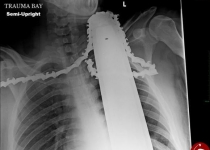

1.دریده شدن گردن و شانه مصدوم با تیغه اره موتوری

بی‌احتیاطی چوب‌بر اهل پنسیلوانیای آمریکا باعث حرکت عقب‌گرد تیغه و پاره شدن نواحی گردن و شانه‌اش شد. وی خوشبختانه در پی این حادثه موفق شد به طور معجزه‌آسایی هشیاری خود را حفظ کند، از درخت پایین آمده و نزد همکارش برود. همکار او زنجیر و تیغه را از بدن مصدوم خارج نکرد تا از صدمات بیشتر آن جلوگیری کند.

خوشبختانه، فرد پس از منتقل شدن به بیمارستان مورد جراحی قرار گرفته و بهبود یافت. گفته می‌شود، تیغه در فاصله یک سانتیمتری از شاهرگ، به گردن فرد اصابت کرد.